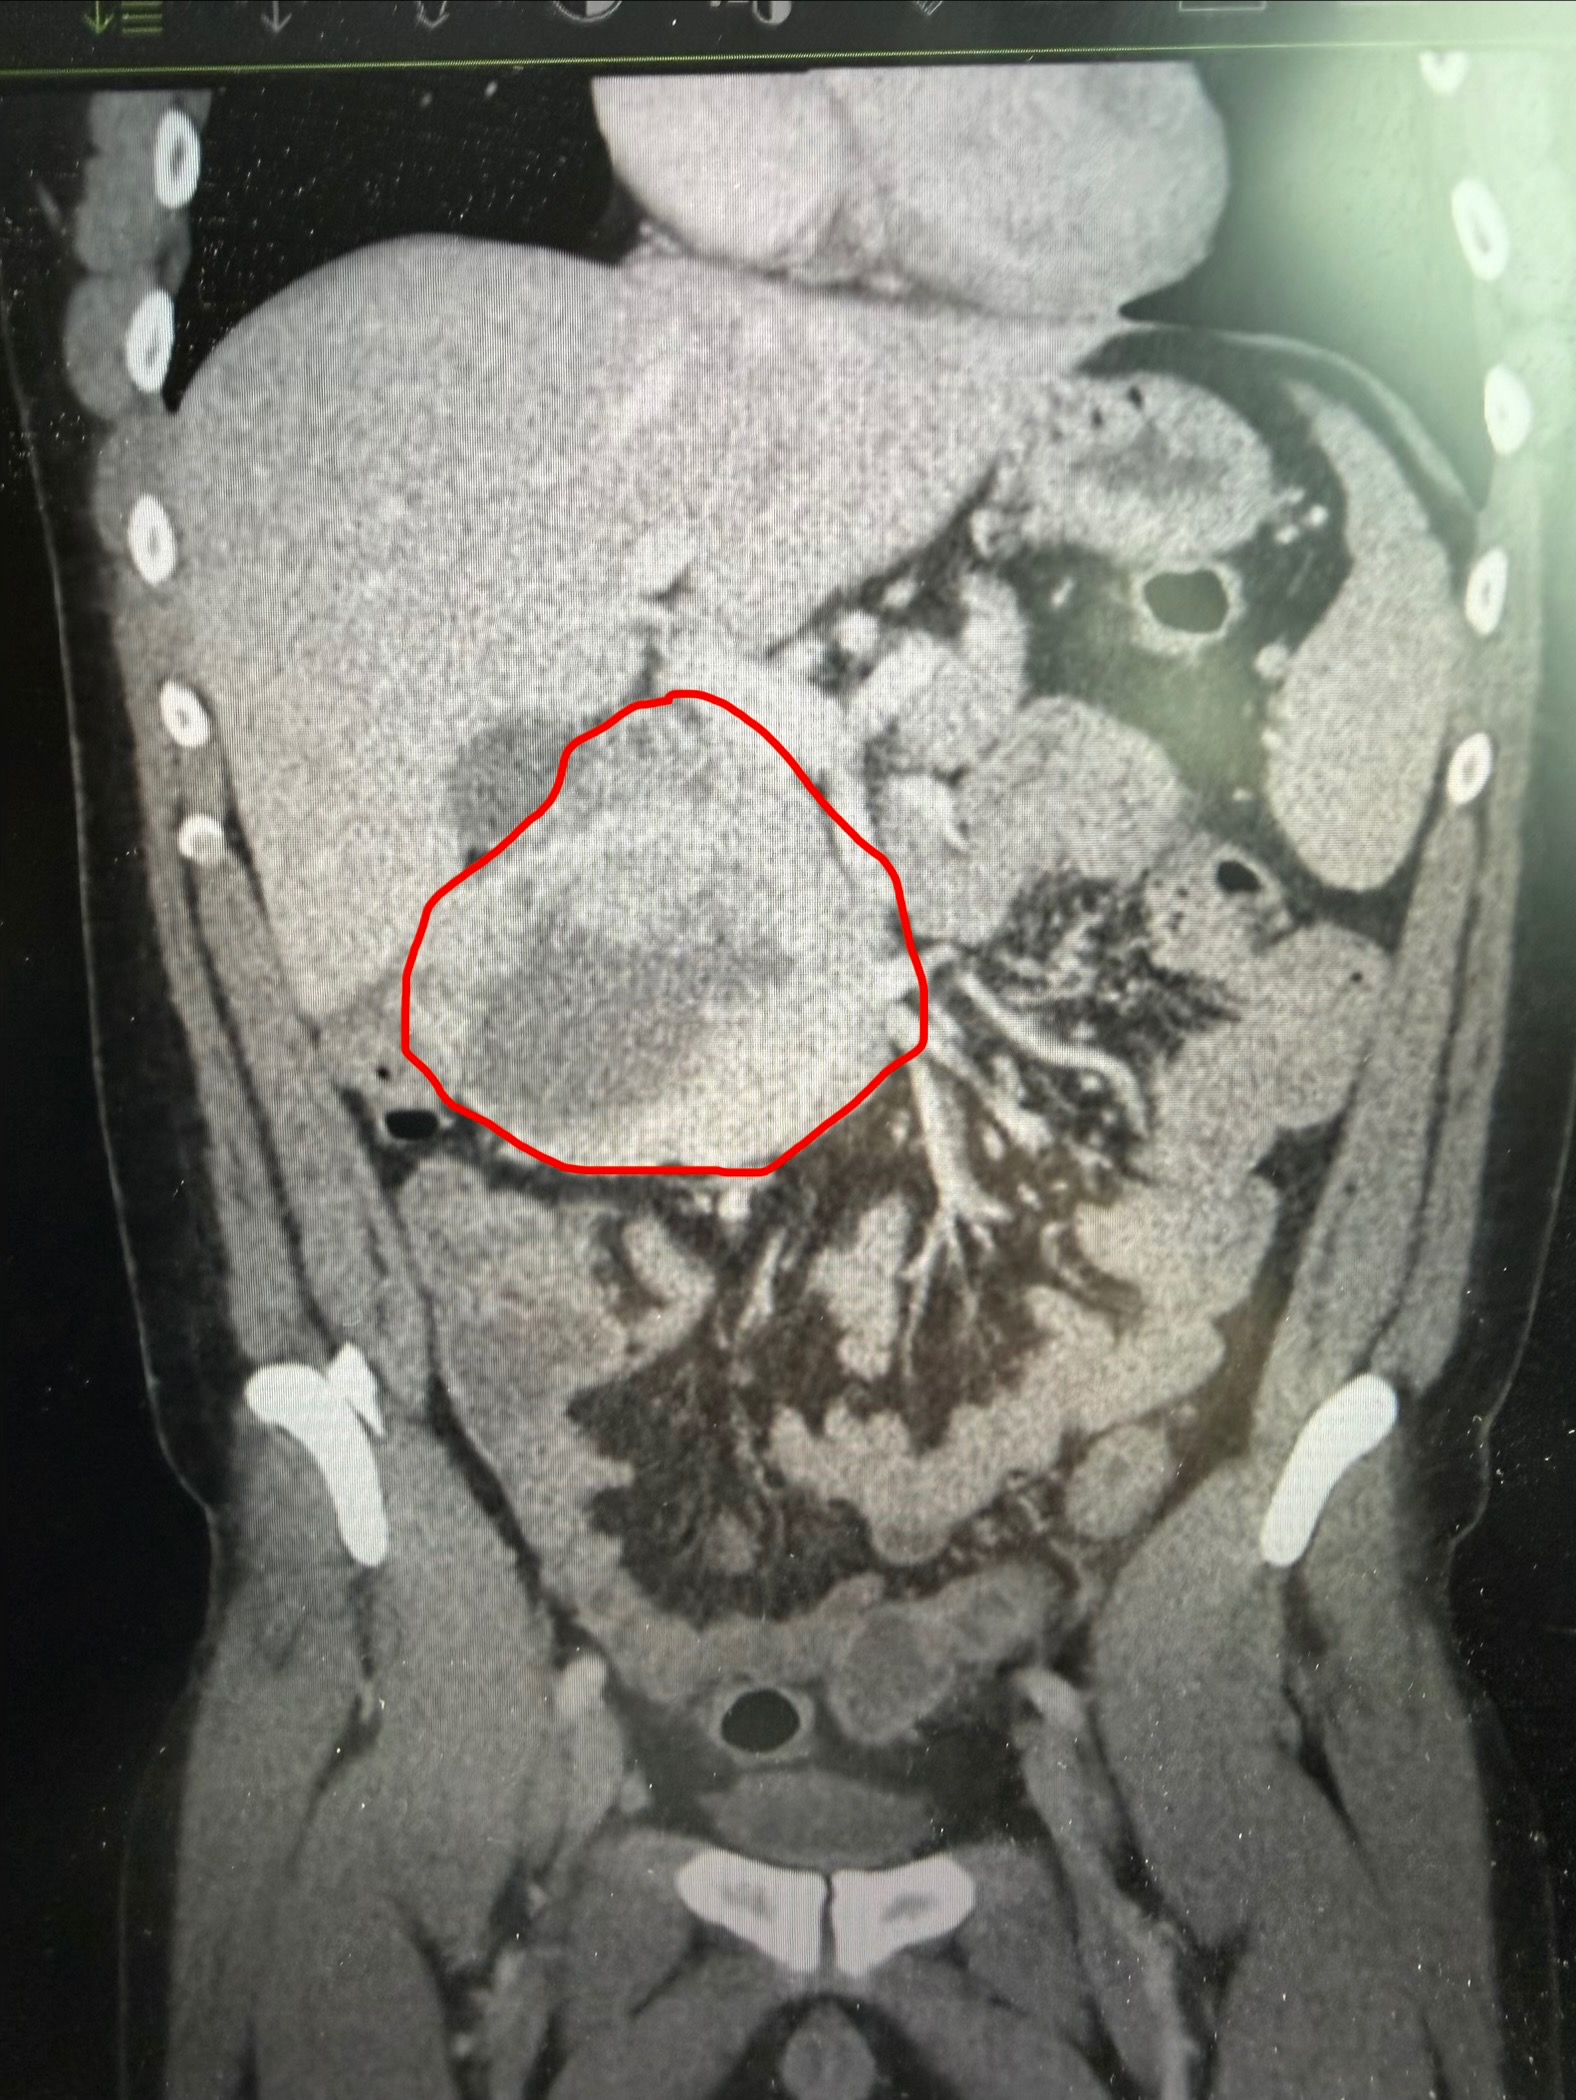

Kyle was having some horrible stomach pain among several other alarming symptoms, for several days, that landed him in the ER Tuesday night. After some bloodwork and a CT scan, he was admitted to the hospital for a large mass in his small intestines. Several possibilities were named as to what this could be, but until we got a biopsy with testing done, we did our best not to panic and stayed positive. Wednesday was a full day with no testing or answers, but Thursday was a busy day. After one failed Endoscopy in the AM, to obtain a biopsy for testing, we did have a successful biopsy, guided by Ultrasound that evening. But, of course, we have to wait for results.

Kyle has been diagnosed with GIST, or a Gastrointestinal Stromal Tumor. A very rare cancer typically found in adults aged 40-70. There is a genetic mutation that causes this cancer, however we don’t know what that is at this time. The doctor is hopeful for the success of removal of this mass, but until we hear from the GI Doctor and Surgeon, we won’t know a definite answer as to what our immediate future will look like. And furthermore, once the surgeon is able to perform the surgery, we won’t know for sure whether or not, it will require more mass removal if it did spread or not.